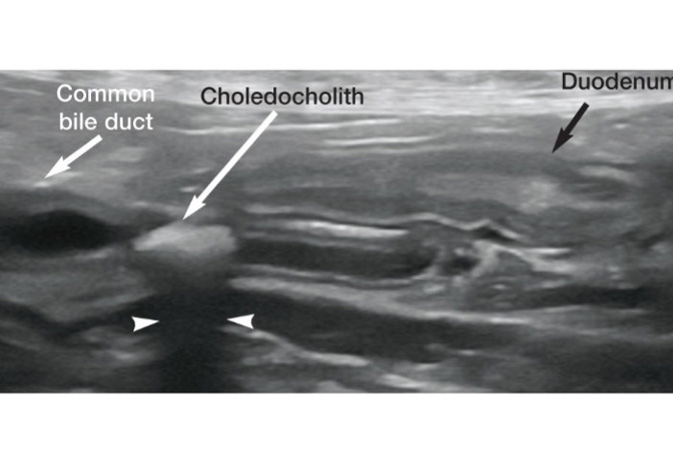

Ultrasonography showed the presence of mucocele and biliary stones (cholecystolithiasis).

Surgery is indicated in these cases to remove the stones from the common bile (CBD) and cystic ducts. To prevent rupture of the gall bladder it is removed also. Our surgeon performed the complex procedure. Inflammation indicative of infection was observed, and intravenous antibiosis (cefuroxime) was begun. After visual inspection of the organs, bile duct patency was checked and duodenotomy was performed to access the end of the CBD. The stones were removed, and duct was flushed. Duodenotomy was closed with simple continuous pattern. Cholecystectomy was performed (cystic duct was double ligated with non-absorbable suture material). The common bile duct was protected. A small cut biopsy was performed using a combination of electrosurgery and suture material. The abdomen was checked for active bleeding and closed routinely. Samples of liver, gall bladder and culture and sensitivity swab were sent for histology, culture & sensitivity. A nasogastric feeding tube was placed to ensure nutrition could be monitored and adequate supplementation could be administered when required.